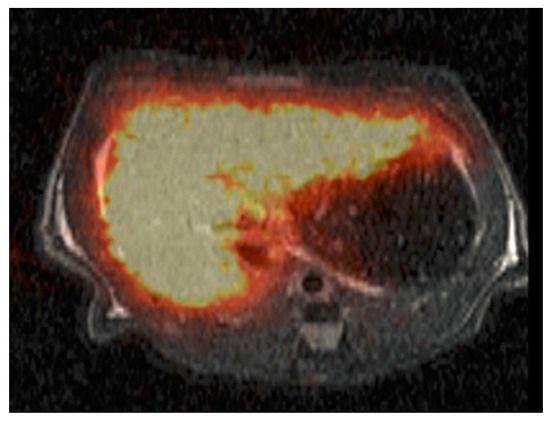

- Ba-Ssalamah, A.; Wibmer, A.; Fragner, R.; Hodge, J.C.; Herold, C.J.; Bastati, N.; Trauner, M.; Bashir, M.R.; Van Beers, B.E. Hepatic gadoxetic acid uptake as a measure of diffuse liver disease: Where are we? J. Magn. Reason. Imaging 2017, 45, 646–659. [Google Scholar] [CrossRef]

- Bae, K.E.; Kim, S.Y.; Lee, S.S.; Kim, K.W.; Won, H.J.; Shin, Y.M.; Kim, P.N.; Lee, M.-G. Assessment of hepatic function with Gd-EOB-DTPA-enhanced hepatic MRI. Dig. Dis. 2012, 30, 617–622. [Google Scholar] [CrossRef] [PubMed]

- Jeong, W.K.; Kim, Y.K.; Song, K.D.; Choi, D.; Lim, H.K. The MR imaging diagnosis of liver diseases using gadoxetic acid: Emphasis on hepatobiliary phase. Clin. Mol. Hepatol. 2013, 19, 360–366. [Google Scholar] [CrossRef] [PubMed]